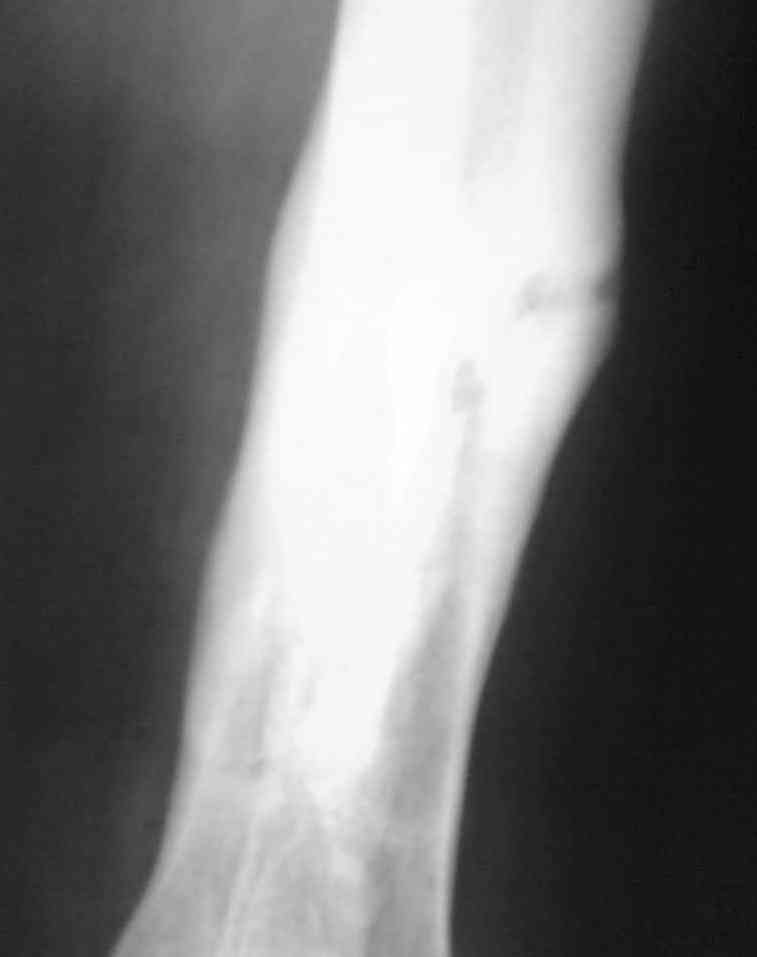

Re: Остеомиелит.

Выкладываю снимки в хронологическом порядке. Снмки все какие есть у больного.